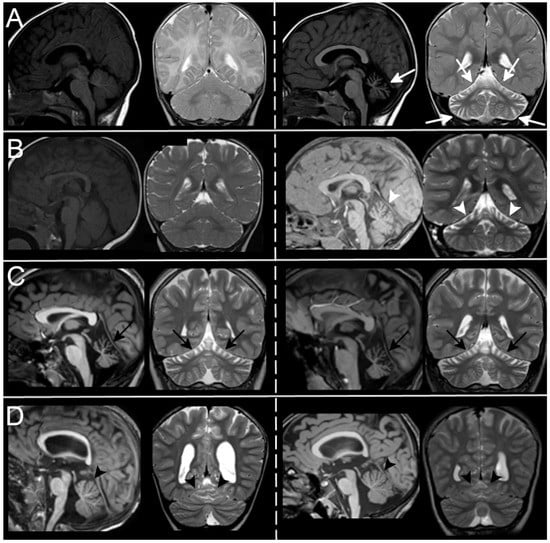

3.3. Neuroradiological Data